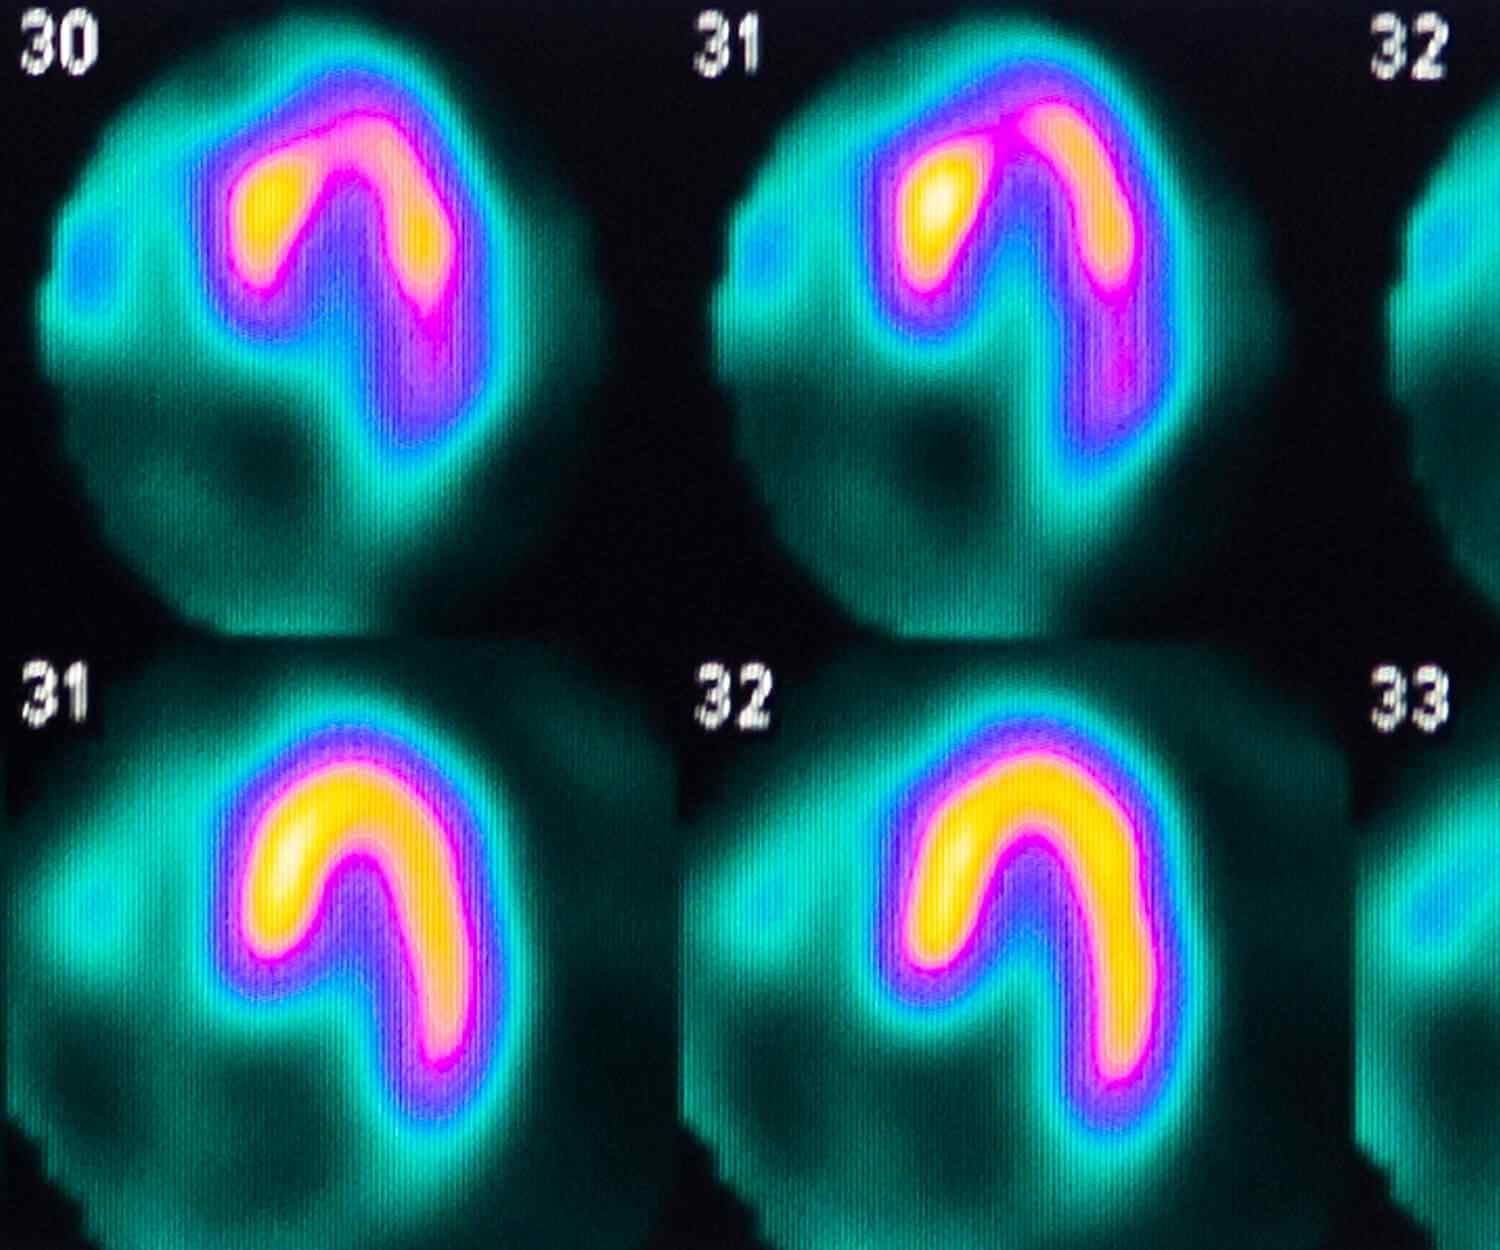

If you have known coronary artery disease, your doctor might recommend the traditional approach because you can also receive treatment during the procedure. Your doctor should give you instructions about how to prepare for CT.